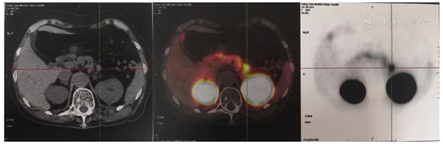

多发性内分泌腺瘤病(MEN)检测:甲状旁腺素(PTH)、胃泌素(Gastrin)阴性,垂体前叶功能正常。胰腺增强CT+灌注:胰体部可见类圆形软组织密度结节影,局部突出胰腺轮廓外,大小约14 mm×11 mm,增强后明显强化,灌注较胰体部正常胰腺组织升高,考虑胰岛素瘤可能大(图1);68Ga-exendin-4 PET/CT:胰体摄取异常增高灶(胰体,大小1.1 cm×1.0 cm,SUVmax 6.4,平均值4.2),为胰升糖素样肽1受体(GLP-1R)过度表达,考虑胰岛素瘤(图2)。

完善患者低血糖症的定位诊断:胰腺灌注CT示胰体部类圆形软组织密度结节影,大小约14 mm×11 mm,增强后明显强化,灌注较胰体部正常胰腺组织升高,68Ga-exendin-4 PET/CT病灶位置与胰腺灌注CT相符,考虑单发胰岛素瘤。